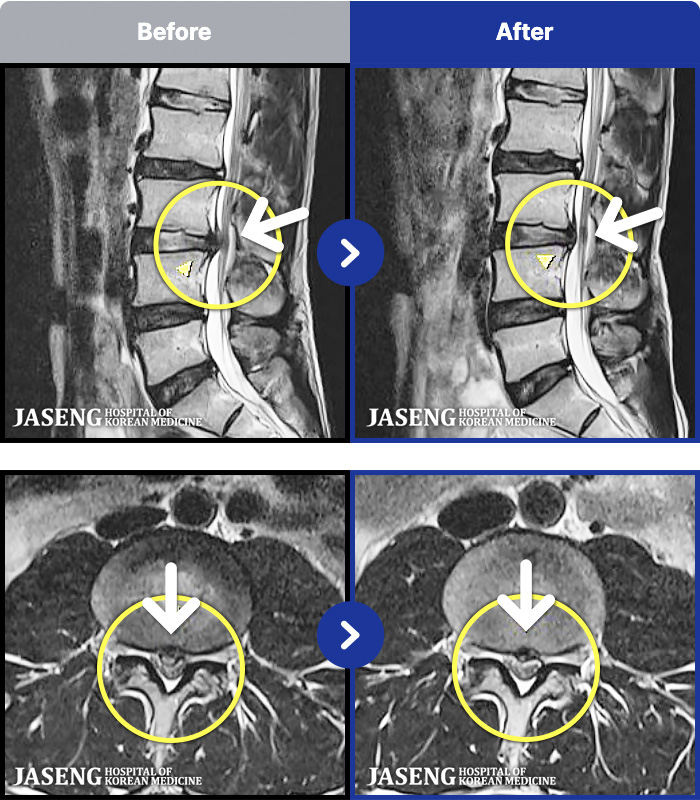

MRI ġ

1,299 MRI ũ ʸ Ȯϼ.